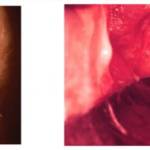

Зачастую описанных пациенткой жалоб достаточно, чтобы гинеколог предположил наличие кольпита. Но для подтверждения предполагаемого диагноза необходимо провести определенные исследования. Прежде всего, врач обязательно проведет гинекологический осмотр. Введение гинекологического зеркала во влагалище вызывает у пациентки с кольпитом боль. При осмотре слизистой оболочки врачу удается обнаружить ее отечность, покраснение, наличие гнойных или серозных налетов.